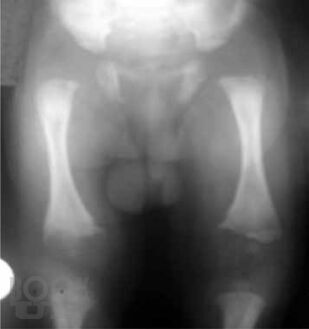

В пособии освещены современные концепции этиопатогенеза наиболее распространенных хирургических заболеваний детского возраста – гнойно-воспалительных заболеваний мягких тканей; различных форм гематогенного остеомиелита; деструктивных пневмоний; бронхоэктатической болезни; гнойно-воспалительных заболеваний мочевыделительной системы и органов брюшной полости – их диагностика и дифференциальная диагностика, современные методы консервативной терапии и оперативного лечения; критерии диагностики сепсиса и принципы рациональной антибиотикотерапии у детей. Пособие предназначено для студентов, обучающихся по специальности «Педиатрия», «Лечебное дело», «Медико-профилактическое дело».